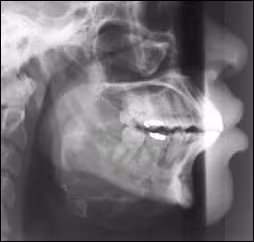

A lateral cephalometric radiograph (Figure 8) showed essentially the same features. The uninvolved right inferior border of the mandible could be easily visualized through the destructive radiolucent lesion in the left mandible. The lower border of the left mandible appeared to be bowed inferiorly by the expanding mass, a feature that was not as clearly appreciated in the panoramic film. A very thin but intact layer of cortical bone appeared to be present covering this expansion of the inferior border.

Figure 8. Lateral cephalometric radiograph demonstrates the inferior expansion of the mass in the left mandible, producing the submandibular extension seen clinically. The radiolucent destruction of the left mandible allows clear visualization of the right mandible through the lesion.